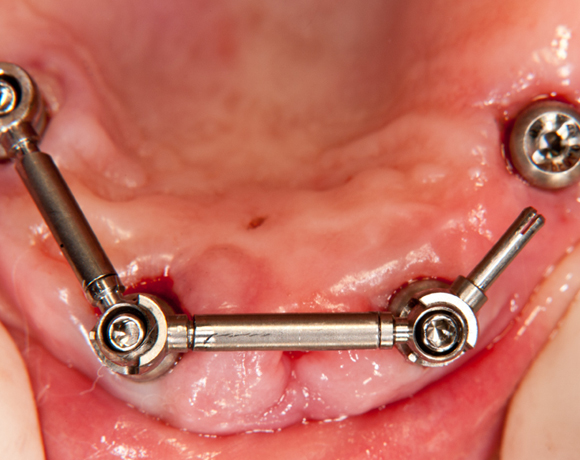

Der SFI-Bar® ist die innovative Steglösung für die abnehmbare Prothetik auf 2-6 Implantaten im Ober- und Unterkiefer.

Mit einer überschaubaren Zahl an präfabrizierten Systemkomponenten lassen sich schnell passgenaue Stegversorgungen für praktisch jede klinische Situation herstellen.

Der SFI-Bar® ist kompatibel mit einer Vielzahl von Implantatsystemen. Hier ein Beispiel mit SPI- Element Implantaten der Firma Thommen Medical AG

2. Passive Fit: Klinisches Ideal erstmals erfolgreich realisiert

+ Spannungsfrei

+ Geringstes Risiko für Implantatverlust

+ Keine physisch starre Verbindung zwischen Implantaten

+ Keine lateralen Spannungen

+ Präfabrizierte, hochpräzise Teile